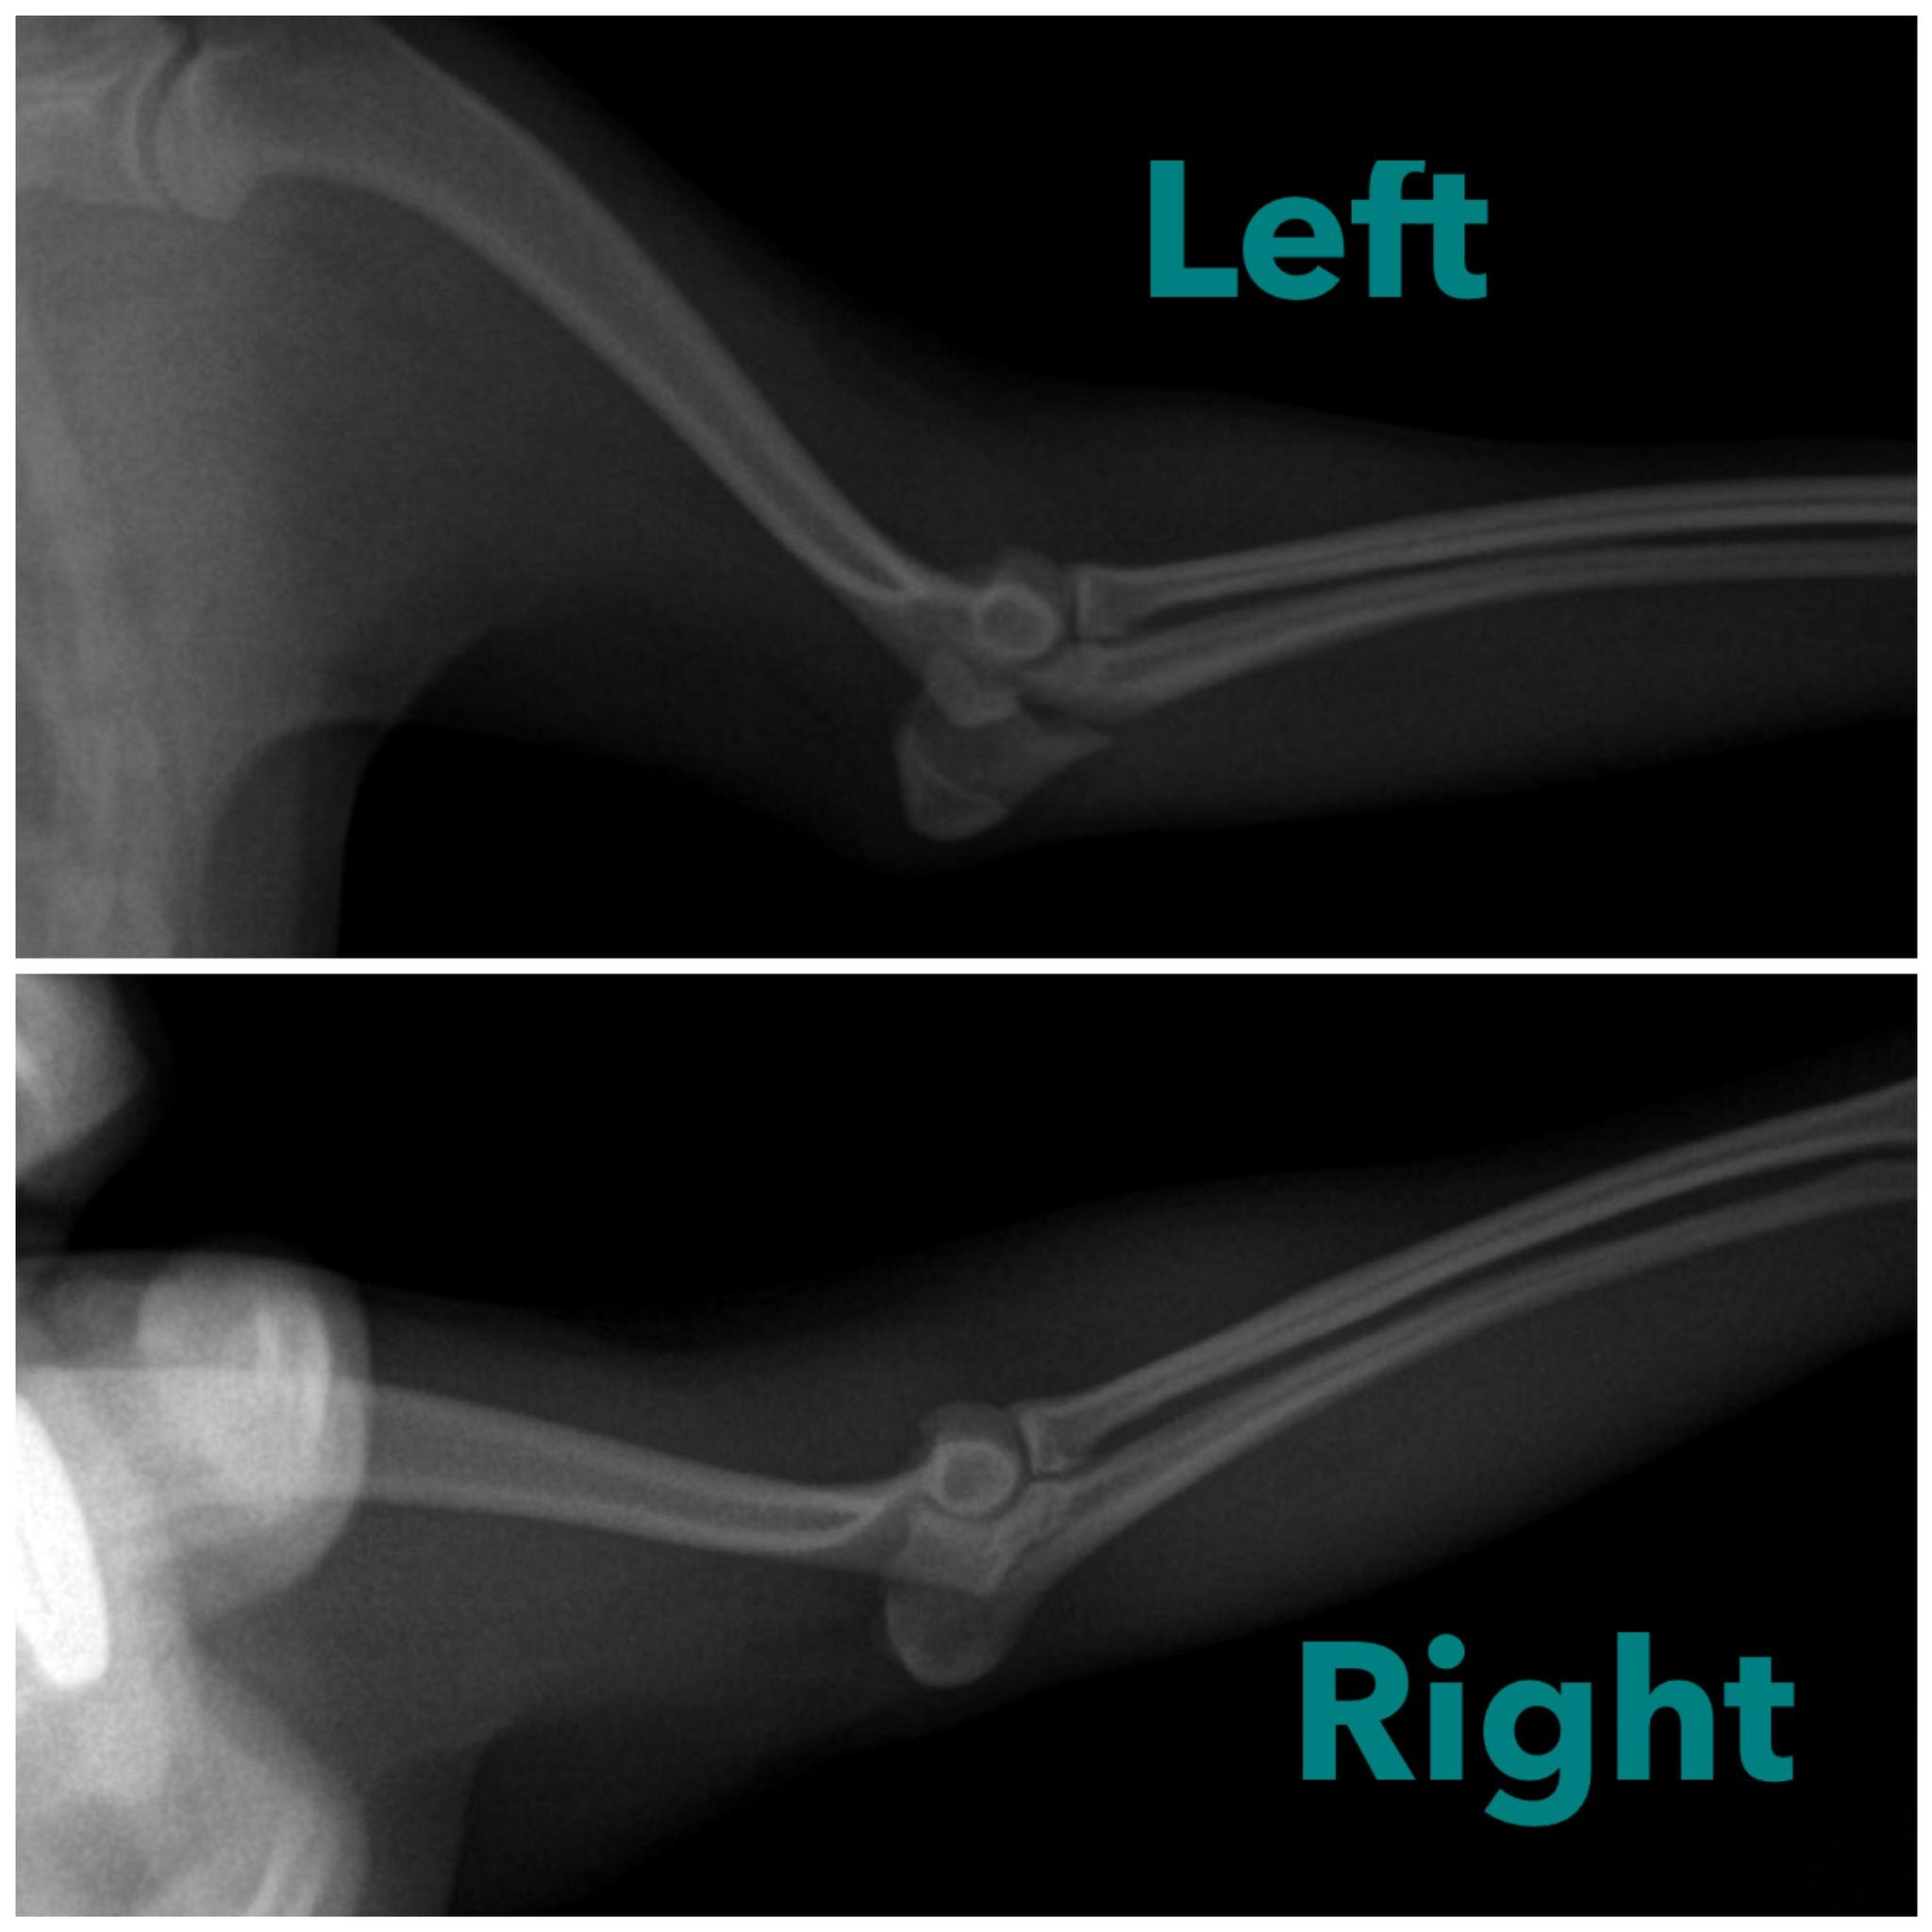

Pet's info: Dog | Pomeranian | Male | unneutered | 1 year and 3 months old | 11 lbs

My dog is pomeranian. Hisleft elbow fractured 3weeks ago Without surgery will it be healed??

Hi, thanks for using Petco Pet Education Center, formerly Petcoach! Sadly that type of fracture should be treated surgically. There is are tendons that attach there and a tension band wire is needed for an avulsion fracture of the olecranon. I would suspect it will not heal. If it has been 3 weeks you should have another X-ray taken to see how it is doing. I wish you the best!